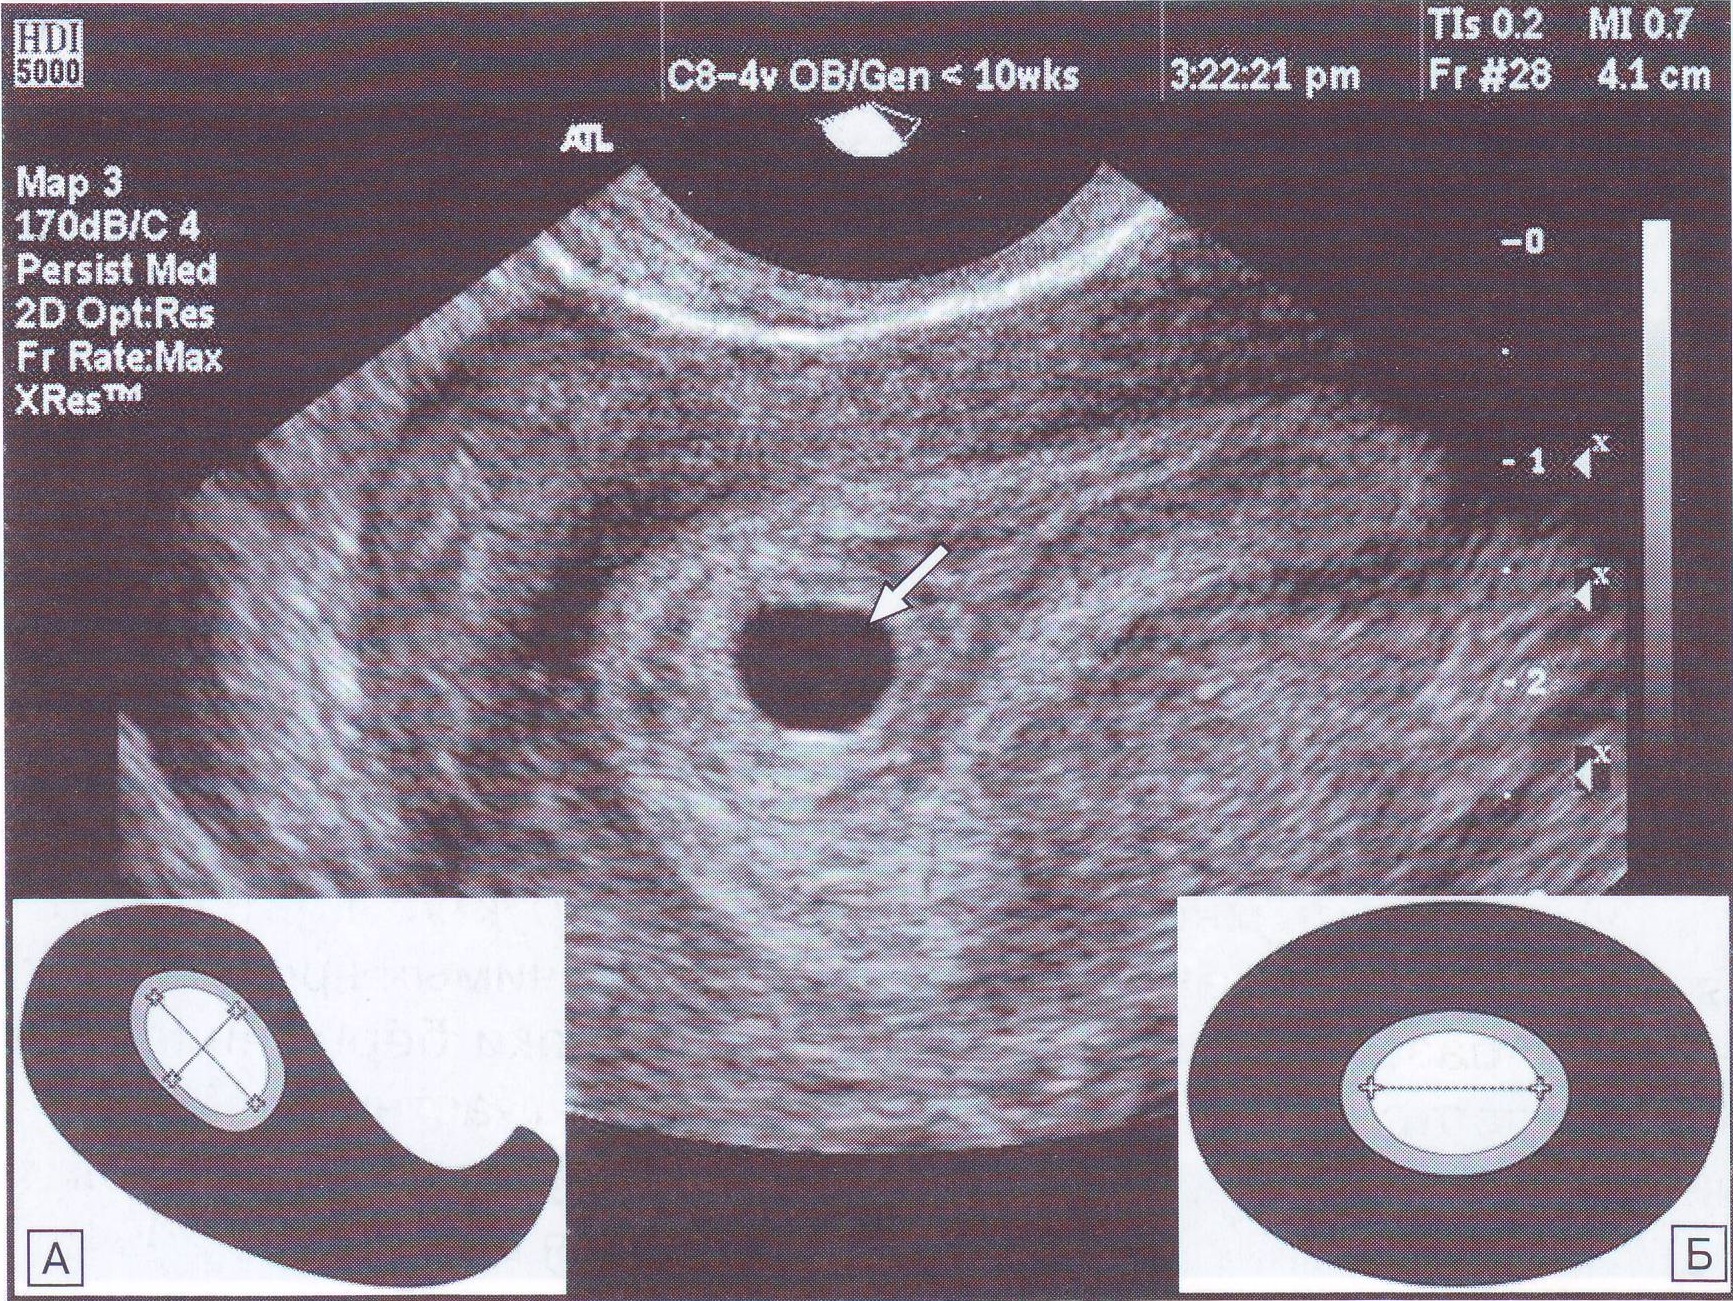

Маточная беременность раннего срока, плодное яйцо

На 4 неделе может быть видно плодное яйцо, но эмбрион еще не всегда визуализируется.

На каком сроке можно увидеть плодное яйцо на УЗИ

Информативность узи на ранних сроках беременности